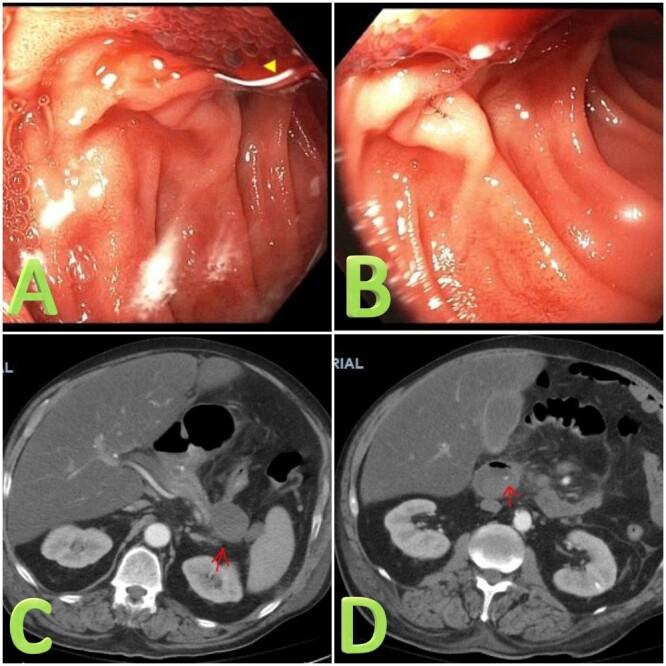

Hemosuccus pancreaticus (HP) is defined as bleeding from the ampulla of Vater through the pancreatic duct. It is a rare complication associated with acute or chronic pancreatitis. The source of bleeding can be from the pancreas itself or surrounding vessels, with the splenic artery most commonly involved. Diagnosing HP is challenging and computed tomography angiography remains the gold standard for diagnosis. We present the case of a 62-year-old male with recurrent pancreatitis complicated with HP. Imaging and endoscopy were consistent with bleeding from the section portion of the duodenum, which resolved without intervention.

胰源性出血(HP)定义为通过胰管从 Vater 壶腹出血。它是一种与急性或慢性胰腺炎相关的罕见并发症。出血来源可能是胰腺本身或周围血管,最常累及脾动脉。诊断 HP 具有挑战性,计算机断层扫描血管造影术仍是诊断的金标准。我们报告一例 62 岁男性复发性胰腺炎合并 HP 的病例。影像学和内镜检查结果与十二指肠节段性出血相符,未经干预出血自行缓解。